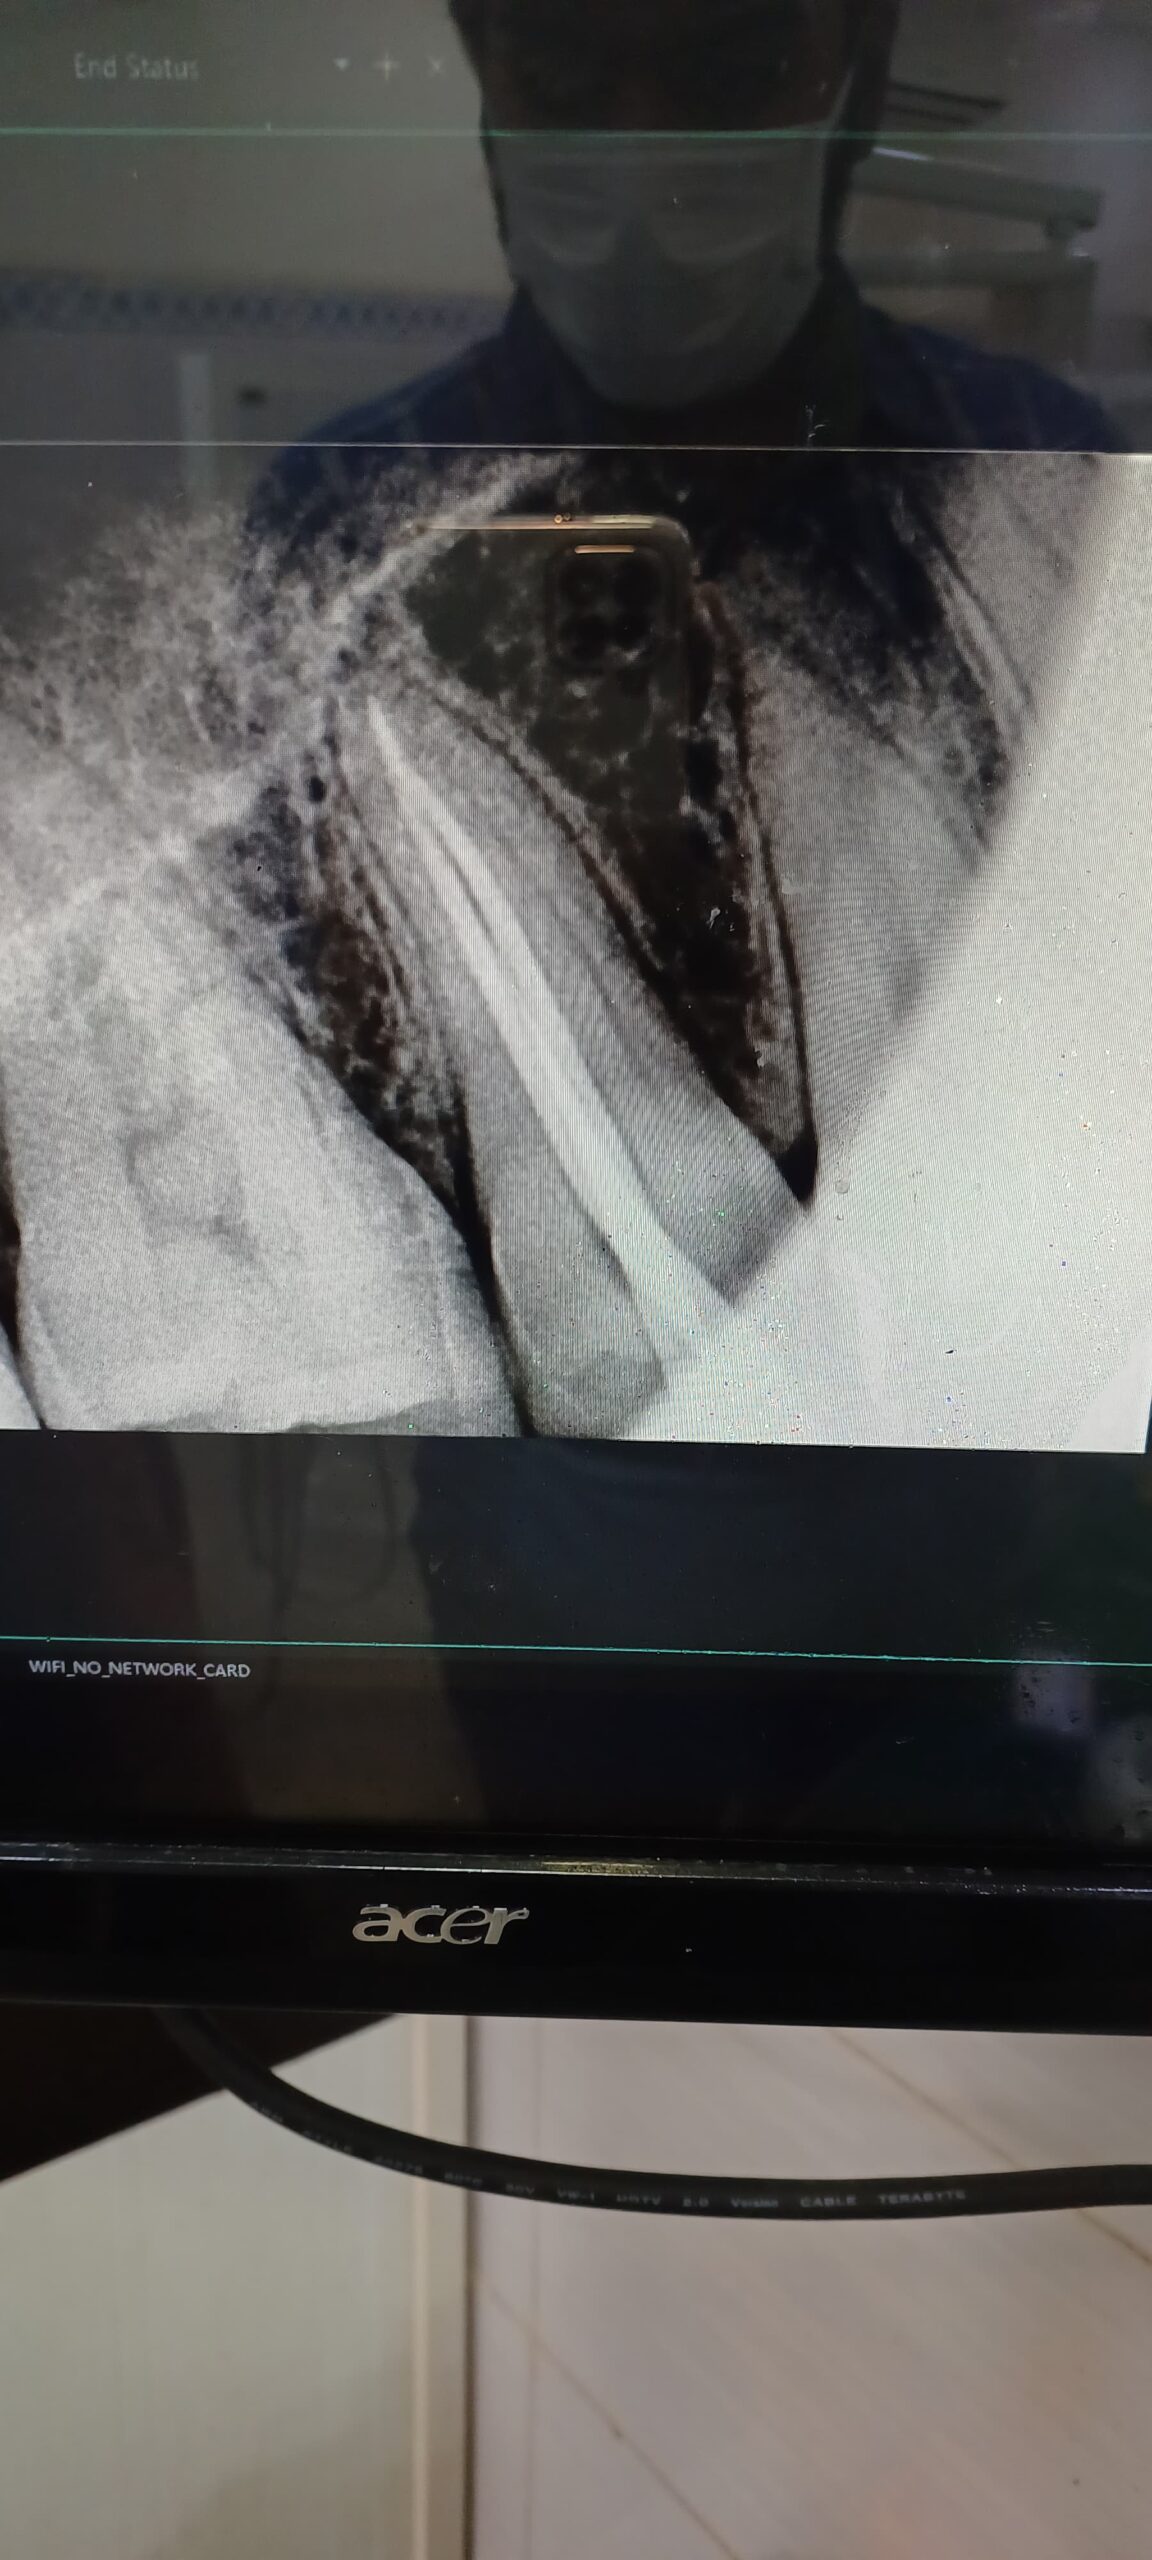

Gallery Home Gallery Pulpectomy Broken File Retrieval Root Canal Treatments Orthodontic Treatments Wisdom Teeeth Removal